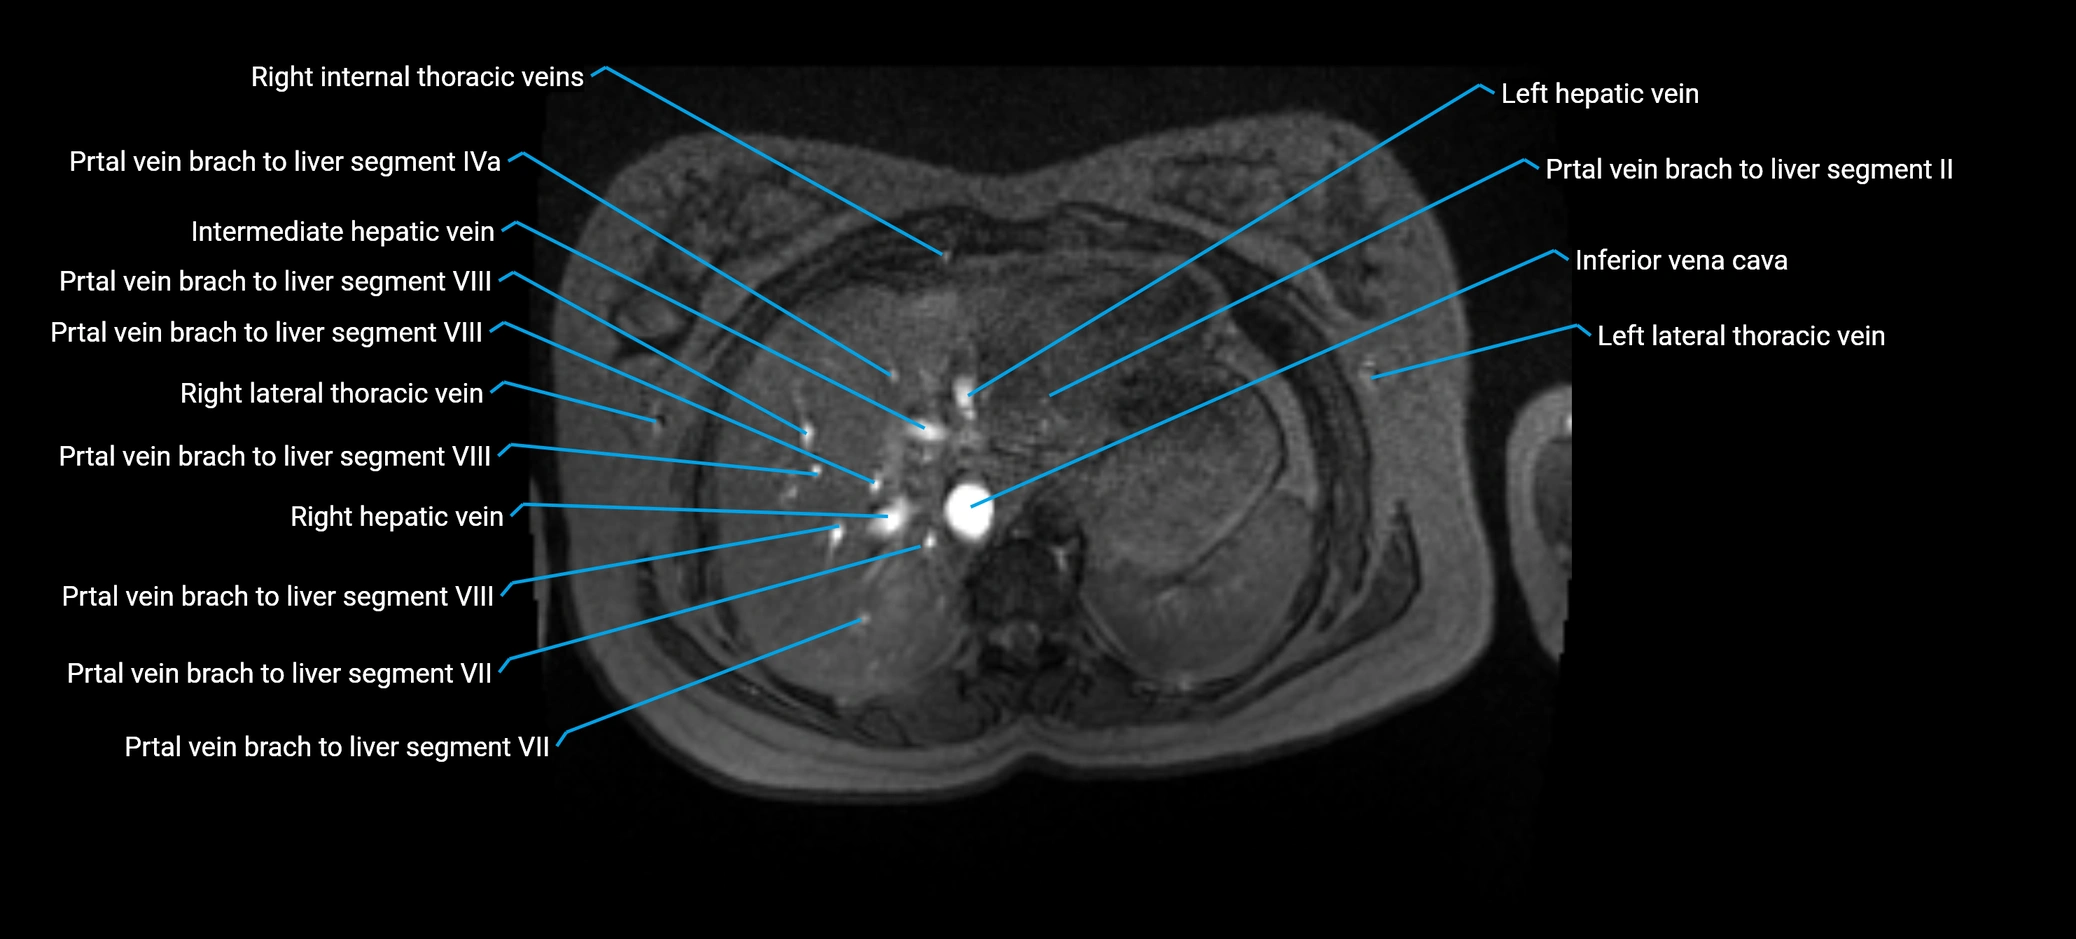

MRI image

image